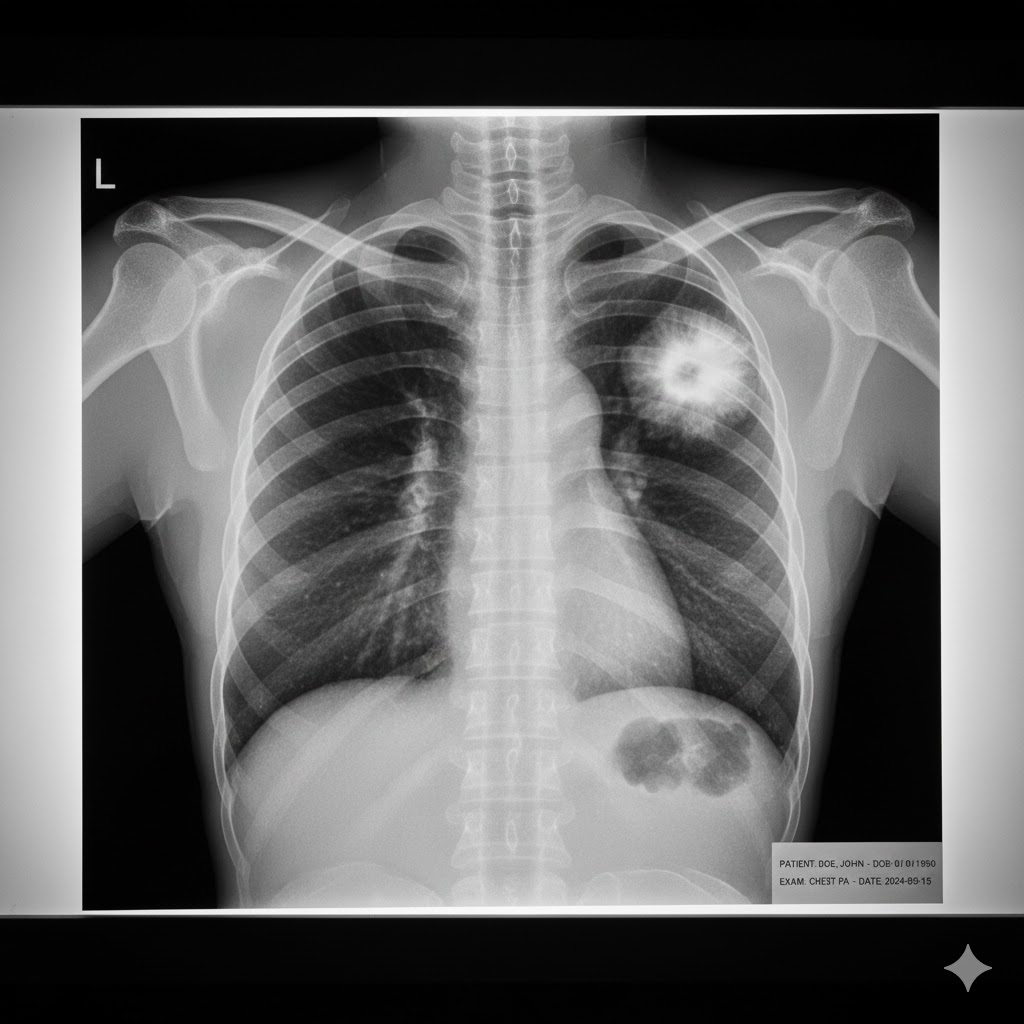

If lung cancer is suspected, a combination of tests will be utilized for both diagnosis and staging (determining the extent of the cancer).

Imaging Tests such as a Chest X-ray or CT (Computed Tomography) Scan are used to identify suspicious areas. Low-Dose CT (LDCT) is the only recommended screening tool for high-risk individuals (those with a long smoking history, current smokers, or those who quit within the last 15 years, usually aged 50–80). A PET (Positron Emission Tomography) Scan is typically used to check for the spread of cancer to other parts of the body (staging).

A Biopsy is the definitive and only way to confirm a cancer diagnosis. A small sample of tissue is removed using a procedure like a bronchoscopy or a CT-guided needle biopsy. This sample is then meticulously examined under a microscope. Furthermore, Molecular Testing of the biopsy tissue is essential for advanced cases, as it checks for specific gene changes (mutations) that can inform targeted treatment options, particularly for NSCLC.